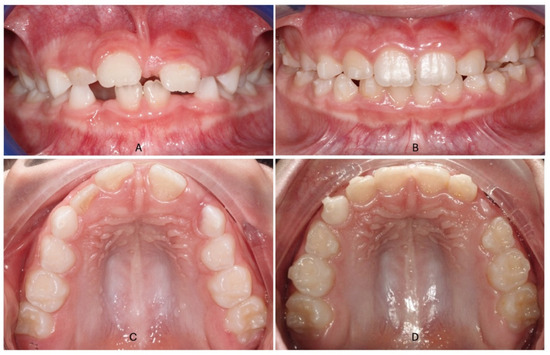

Figure 2.

Intraoral photos of Invisalign first treatment in a patient with a contracted upper arch a no cross-bite: (A) (pre-treatment frontal view); (B) (post-treatment frontal view after Invisalign expansion protocol); (C) (pre-treatment occlusal view); (D) (post-treatment occlusal view).